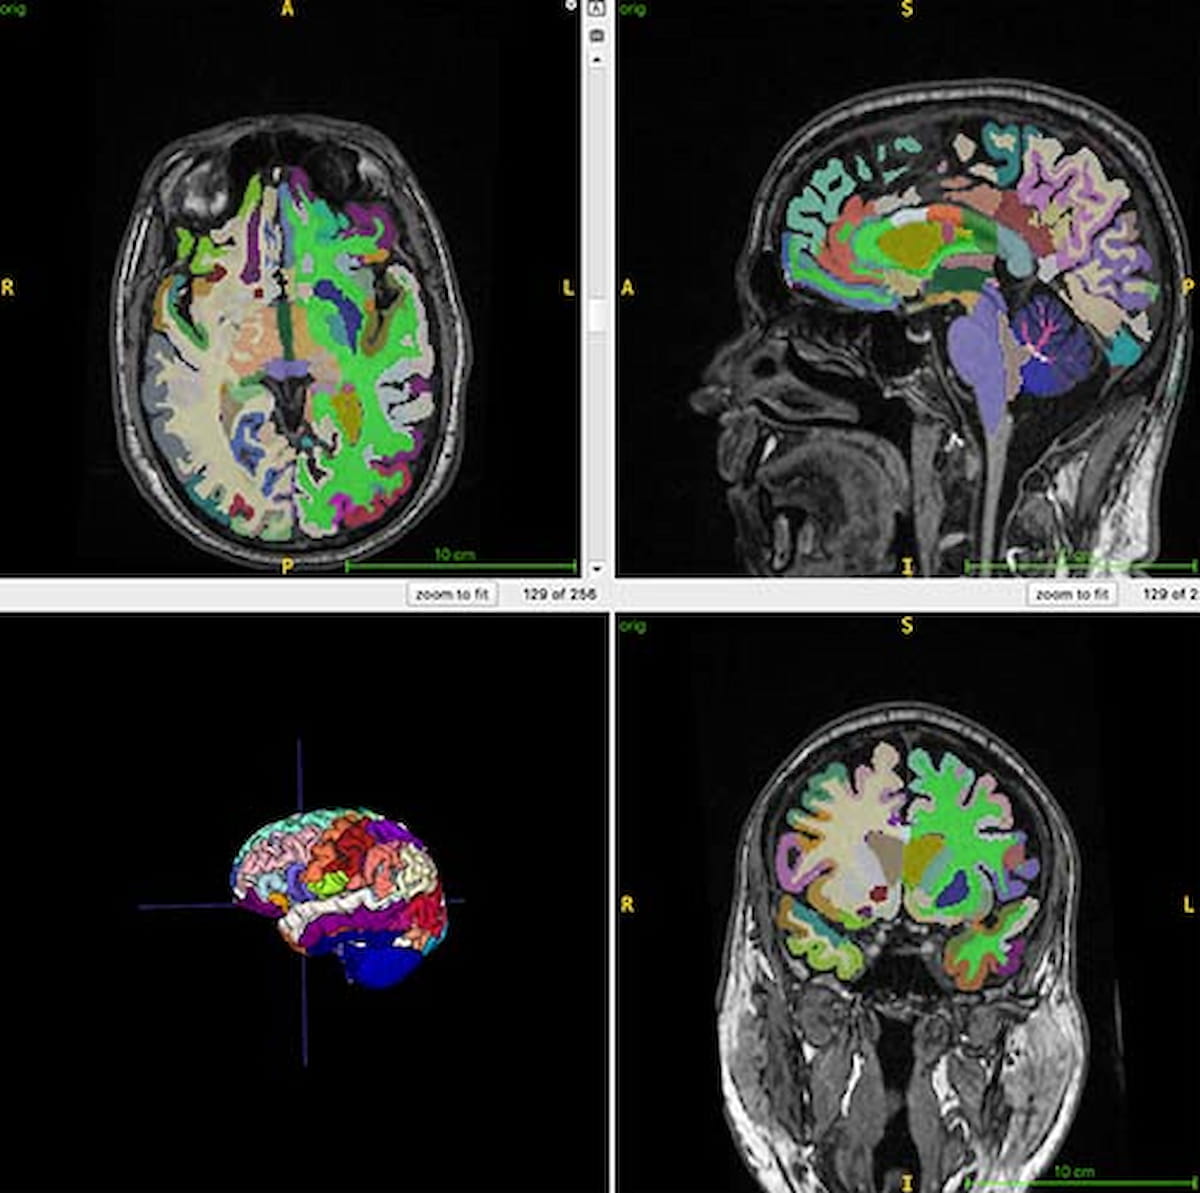

Researchers at the upcoming Radiological Society of North America (RSNA) conference have presented findings suggesting that a combination of higher muscle mass and lower visceral fat may positively impact brain aging. The study involved 1,164 healthy participants, assessing muscle and fat volumes through MRI scans. Results indicated that greater total normalized muscle volume was linked to younger brain appearance, while higher visceral fat was associated with older brain age. The study reinforces obesity as a significant risk factor for Alzheimer’s disease and suggests further research into weight loss medications that could help reduce visceral fat and improve brain health.